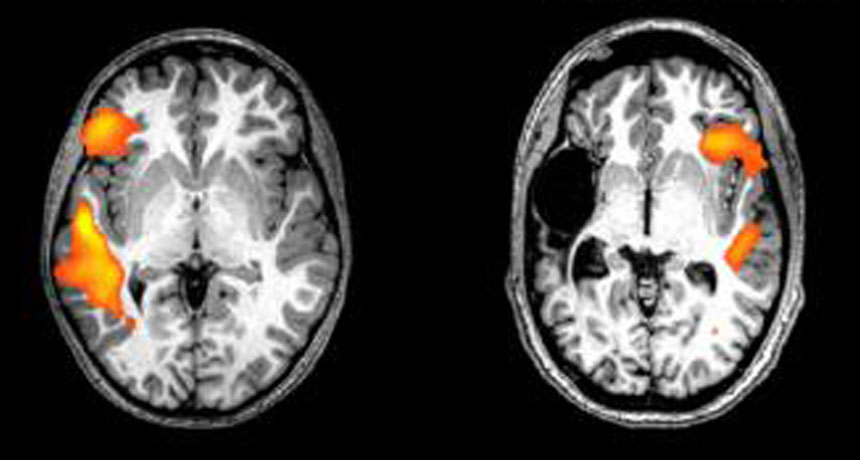

SWITCHING SIDES  These fMRI scans show the brain activity of a healthy person (left) and a stroke patient (right) while doing a language-related task. Having a stroke just before or after being born flips key language-processing areas from the left to the right side of the brain, a new study shows.

E. NEWPORT